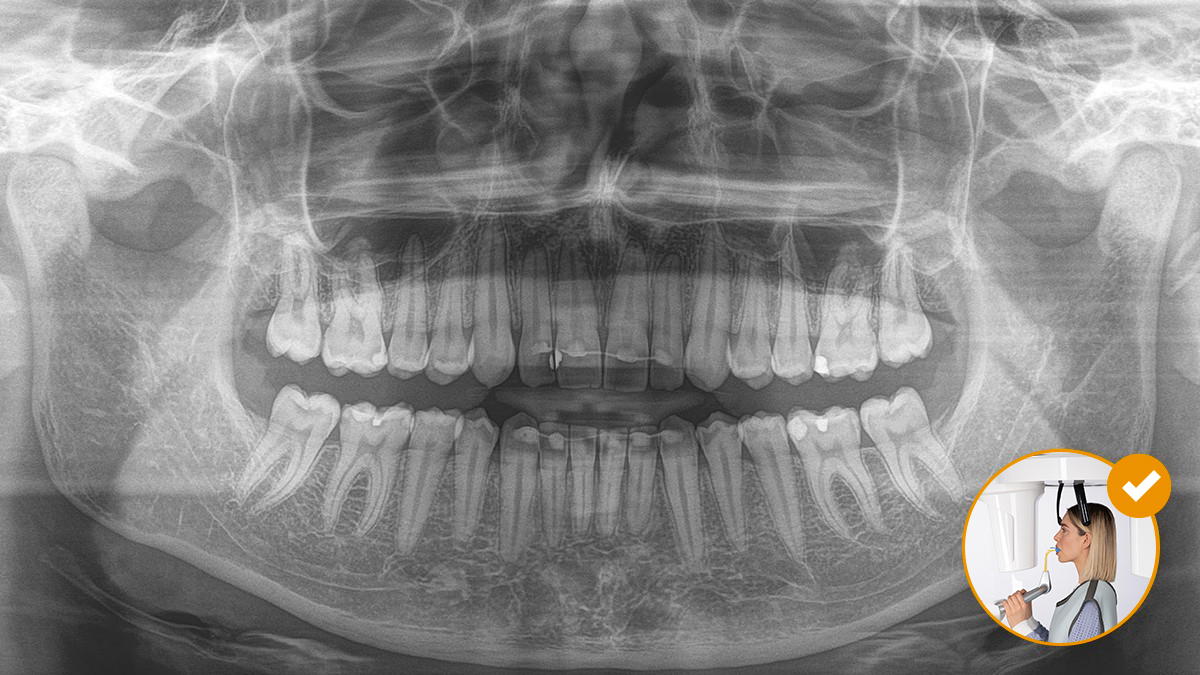

Die korrekte Patientenpositionierung führt zu einer hohen Bildqualität, die eine genaue Diagnose ermöglicht und die Patientenerfahrung erleichtert und verbessert.

Dies ist unser 10-Punkte-Konzept für die einfache Patientenpositionierung und Röntgenbildgebung. Es geht in erster Linie um zwei Dinge: Hochwertige Aufnahme und Komfort für den Patienten und die Assistenten.